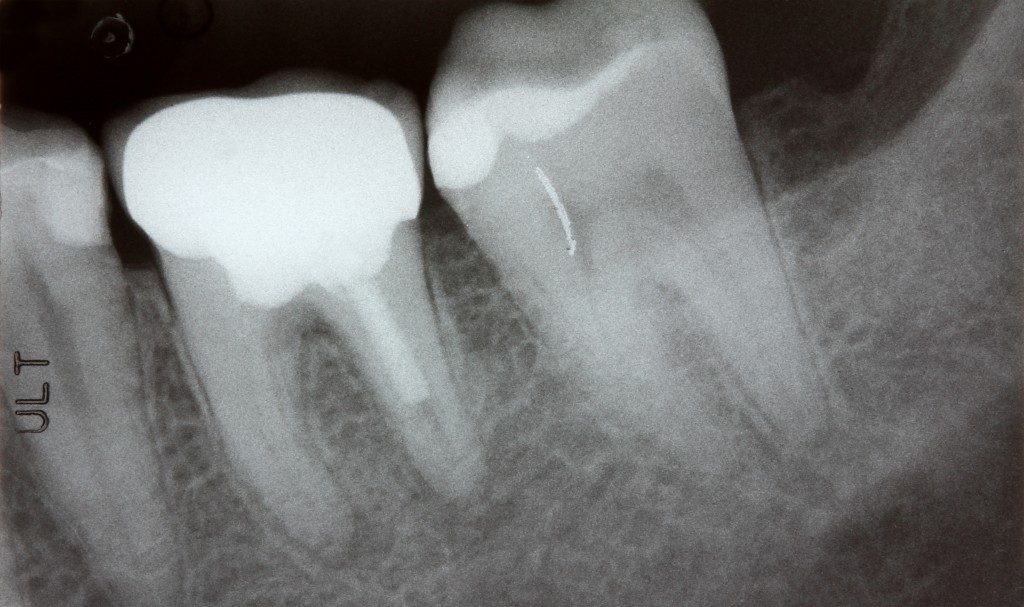

Bakteri Porphyromonas gingivalis yang biasa ditemukan pada gusi telah terdeteksi sampai ke area atrium kiri jantung dan dipercaya dapat menyebabkan jaringan parut yang mengganggu kerja jantung. Jaringan parut ini membuat sinyal listrik jantung kacau dan meningkatkan kemungkinan AFib.